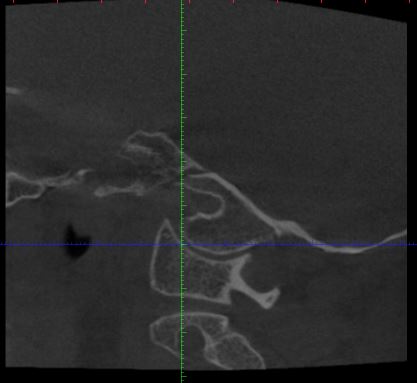

Der HNO Arzt vermutet die Halswirbelsäule als Ursache für den Tinnitus und hat eine DVT anfertigen lassen. Leider kann er die Aufnahmen nicht auswerten und sein Radiologe hat Urlaub. Kann von Euch jemand auf den angehängten Fotos etwas erkennen?